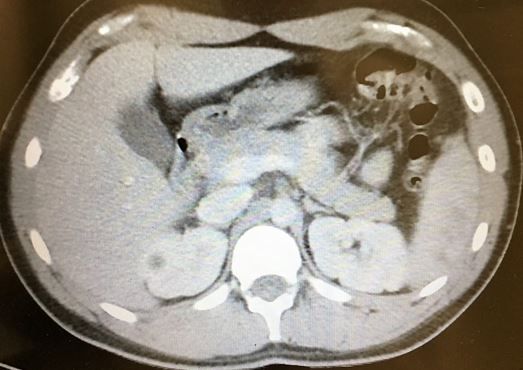

Splenic Injury from The Emergency Medicine 1-Minute Consult Pocketbook